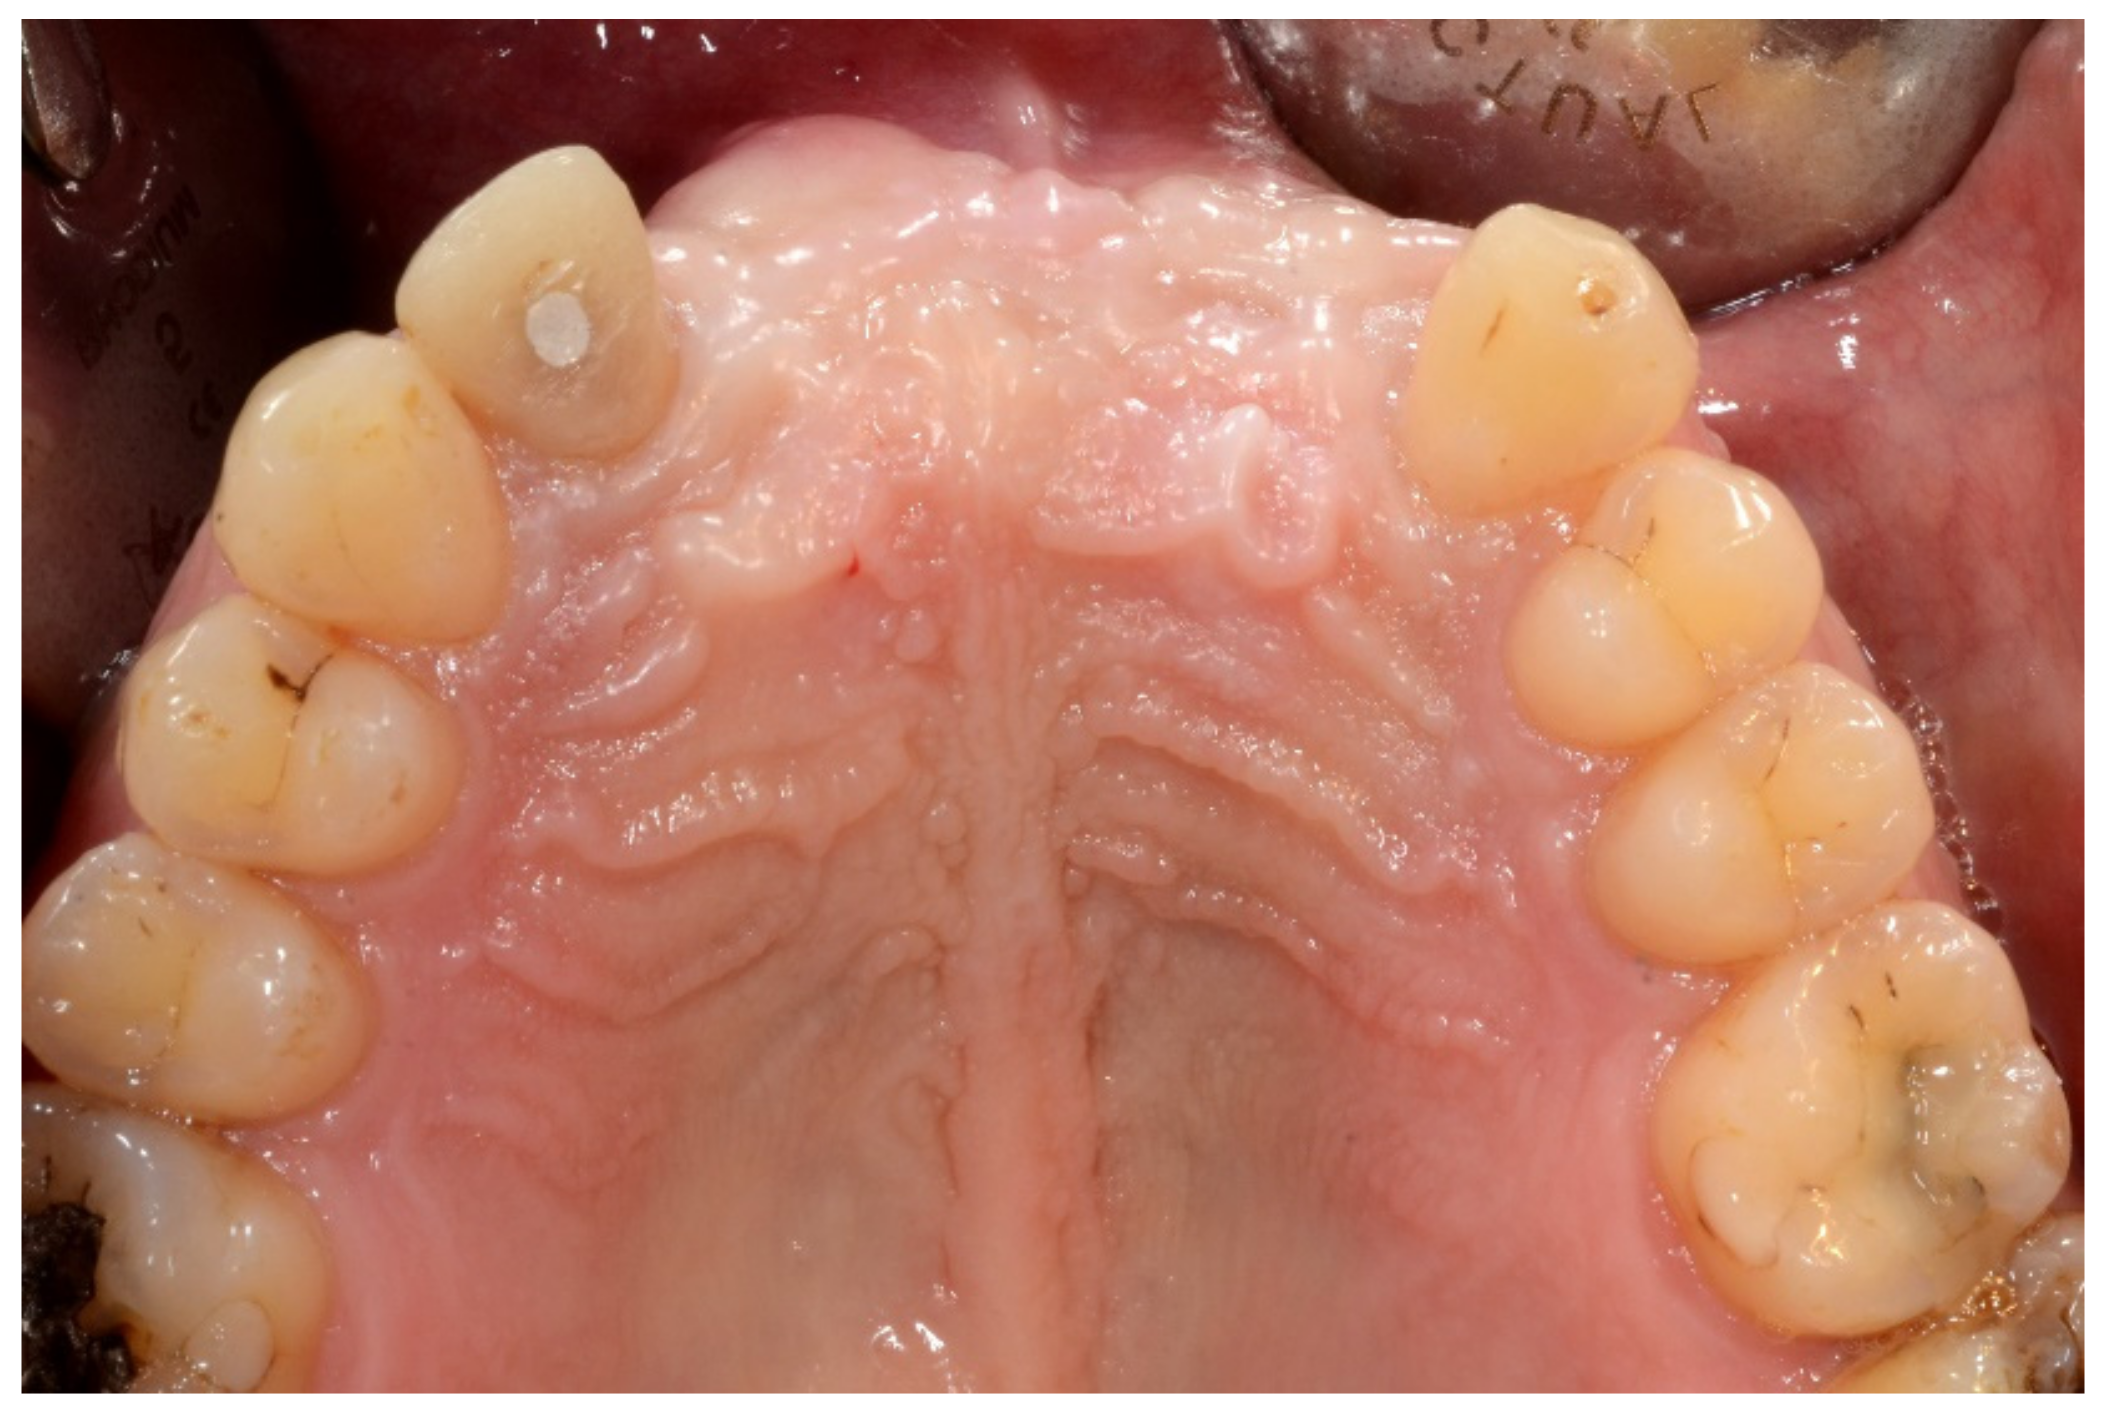

Figure 3.

Three-dimensional (3D) CBCT scan images with the patient wearing the planned prosthesis and 3D images of the prosthesis equipped with integrated radiopaque reference spheres scanned separately.